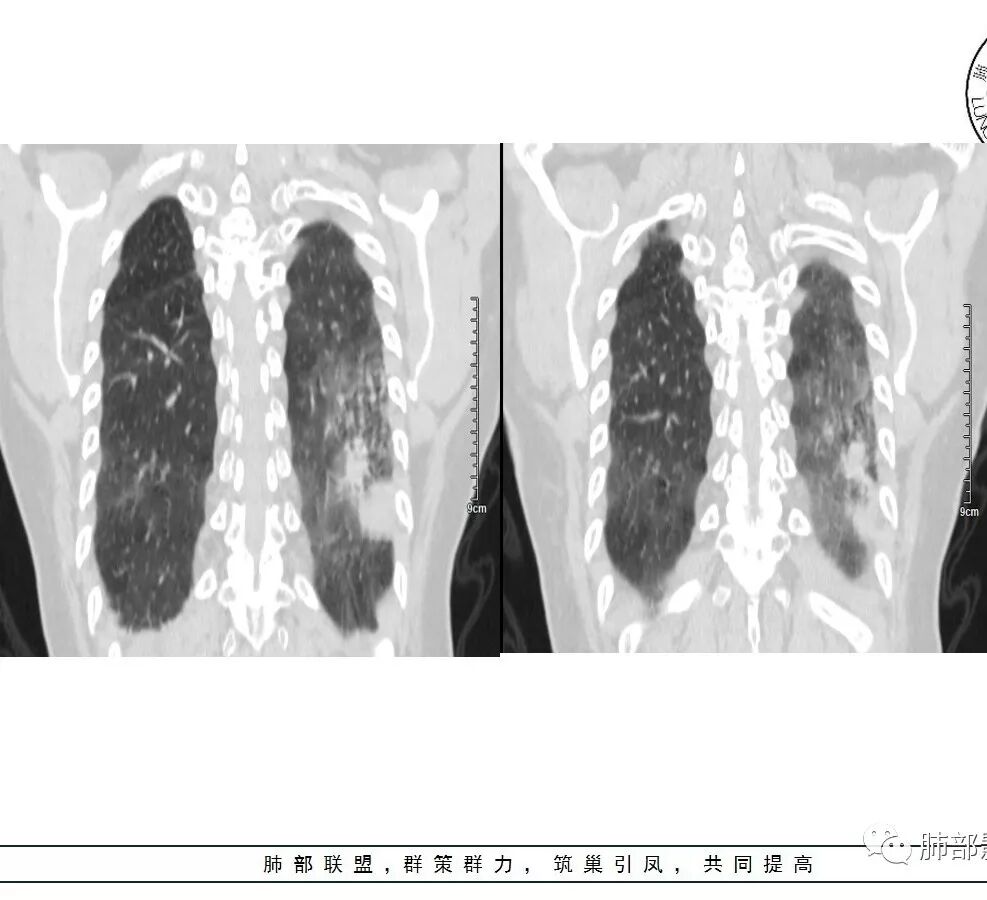

1、主病灶  左下叶斑片状、大片状致密影

2、两肺马赛克灌注

3、两侧肺门区钙化淋巴结

总共就这三大块

这三大块有没有联系?有没有相关性?

这三幅图是连续的,我们看到支气管中间这一幅狭窄了

大——小——大,狭窄后扩张

从这幅图看好像与周围病灶分界不清,支气管腔狭窄后扩张,支持炎性

两肺门钙化淋巴结一般考虑:结核?尘肺?淀粉样变性?

这是老问题:1、肺门区软组织密度影较弥漫;我们常规鉴别的就是结核?鳞癌?既往我们群里基本这两方向。2、弥漫的淋巴结钙化,加上马赛克灌注。马赛克灌注的原因是两个,一个是肺动脉的,一个就是小气道的问题。我们看增强的区域,没有看到栓塞,所以我倾向于小气道的问题,就是弥漫气道病变,慢性气道病变要考虑。我怀疑有没有淀粉样变性累及气道壁改变的可能。淀粉样变性是一个继发性病变,结核也可以,粉尘也可以。

这个病例支气管狭窄后扩张,肺门区有很多钙化的淋巴结,两肺弥漫的马赛克灌注,肺门淋巴结这么多,一个结核,一个尘肺,然后就是一个淀粉样变性,这几种最常见。鳞癌因为老年女性,除非吸烟,不太考虑,又不能绝对排除,所以就把鳞癌放到后。